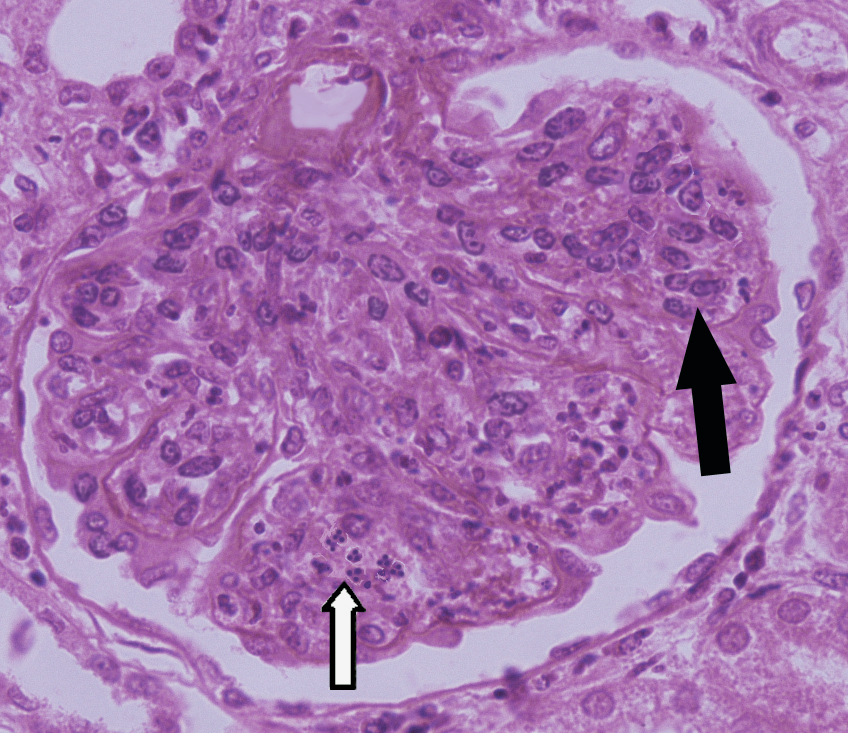

1.Acute glomerulonephritis